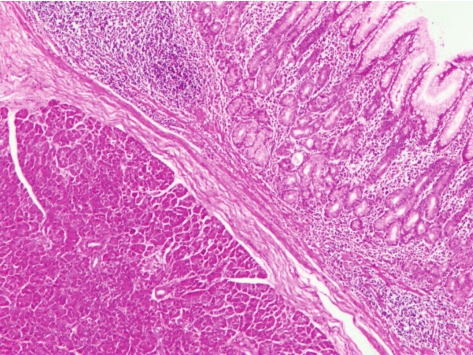

胰腺异位(ectopic pancreas)是一种先天性畸形,是胰腺原基与胚胎原肠粘连或穿透原肠壁,并在发育过程中随原肠旋转而分布于各个异常部位。它与正常胰腺之间无解剖学联系,是孤立的胰腺组织,主要发生于胃,通常位于幽门和幽门窦(图3-8)。胰腺异位罕见发生癌变。

大多数为单发,多发者少见。形状可为圆形或圆锥形,直径约2~4mm,其顶部常呈凹陷,为胰管开口。多位于黏膜下层,少数可位于肌层或浆膜下。

异位胰腺组织主要位于胃黏膜下或肌层,组织学分为3种类型:Ⅰ型可见胰腺导管、腺泡和胰岛,类似正常胰腺组织,较少见。Ⅱ型可见胰腺导管和腺泡,无胰岛,较多见。Ⅲ型可见多量胰腺导管和十二指肠腺,无腺泡或极少,无胰岛,并可见明显增生的平滑肌。

图3-8 胰腺异位至胃窦

胃黏膜下可见异位胰腺腺泡。